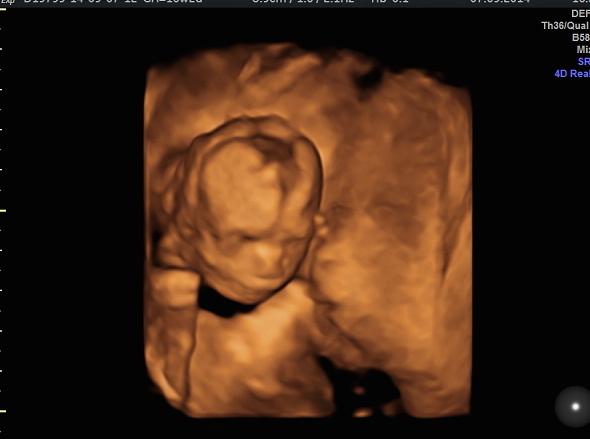

Little boy at 16+2. Kind of just starting to look like a baby!

Awwww that's a fantastic pic, really clear! Cute little face too :) I think they only start to pile on the chub from this stage onwards so it's not surprising he was a little skinny haha.

Those 3d scans are mental! Really brings it all home whats happening in there